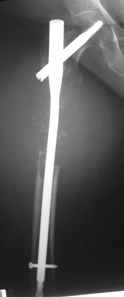

Приветствую, коллеги. 2 года назад пациентке поставлен диагноз саркома бедра,

Реостеосинтез |  Сегодня |  |  |  | 1.5 года назад произведен синтез для улучшения качества жизни для по поводу патологического перелома на уровне открытой биопсии. Через 4 месяца открытый реостеосинтез с исправлением оси и восстановления опроспособности. В период после перелома лучевой и химиотерапии не получала. Месяц назад появилсь возрастающие боли в суставе. Ходит с тростью. Движения в коленном суставе качательные.На рентгеннограммах после реостеосинтеза намечалась тенденция к сращению. В области операционной раны периодически открывался-закрывался свищ. На последних - кроме миграции гвоздя в сустав - лизис костной мозоли. Можно ли одной из причин миграции считать длительную статическую фиксацию гвоздя? У кого-нибудь есть опыт на каких сроках проводить у онкобольных динамизацию? Что можно сделать для ликвидации боли и поддержания опороспособности конечности? Имеет ли смысл установка более толстого фиксатора без дистального блокирования? И вообще,ставить ли здесь вопрос о сохранении конечности?

Саркомные переломы обычно не срастаются, по этому не зависимо от места метастаза фиксатор устанавливается максимально длинный и обязательно с блокировкой что бы сохранять длину кости даже после роста метастаза или при дополнительно метастазировании. В Вашем случае блокировочные гвозди выглядят тонкими и проведены только через один кортекс. Гвоздь толщиной более 10 мм с блокировочными шурупами 4-5 мм проведенные через обе кортикальные пластинки может обеспечить опороспособность даже если перелом не срастется или литический процесс распространится.

Посылаю первый снимок, который попался по руку.